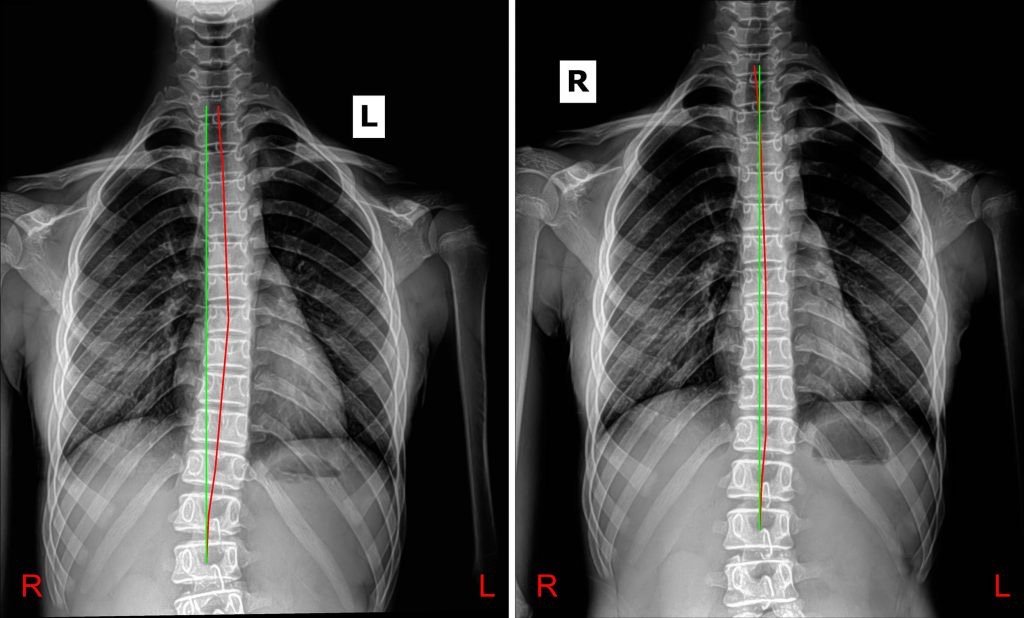

CHIROPRACTOR VS SYRINX

A look at chiropractic care with a syringomyelia patient